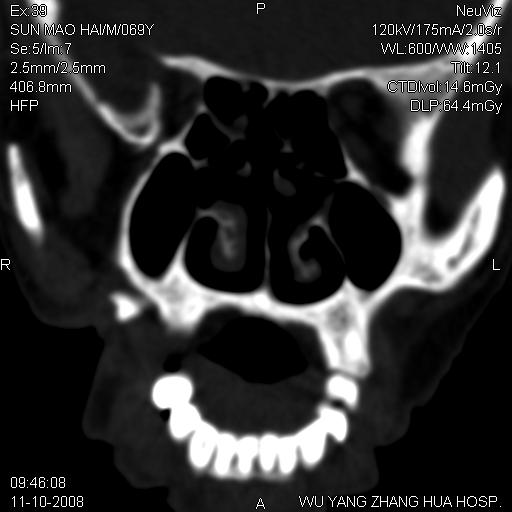

标题: CT16568:右面部瘘管半年余,无其它不适. [打印本页]

标题: CT16568:右面部瘘管半年余,无其它不适.

考虑右上颌异位齿(或斜向阻生齿)并根尖脓肿。

1.右上颌异位齿

2.右上颌化脓性骨髓炎

3.右下鼻甲肥大